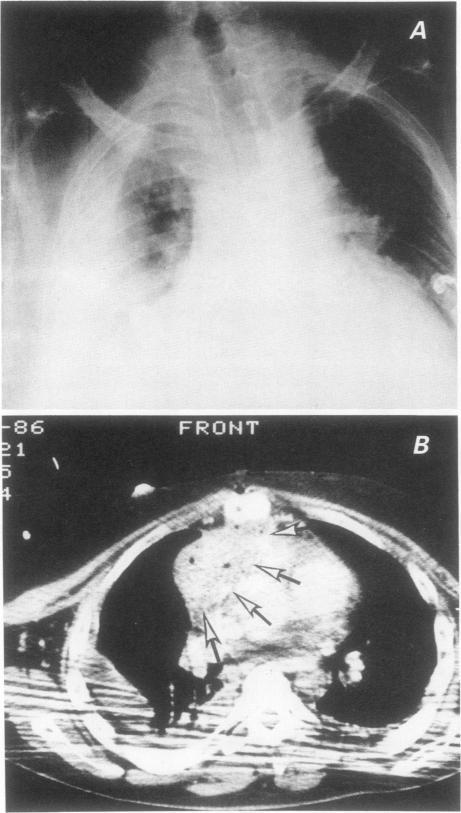

After cardiac transplantation, bacterial mediastinitis is a rare but dangerous early complication. Of the 113 patients who underwent heart or heart-lung transplantation at our hospital from August 1981 to April 1989, 8 developed purulent mediastinitis. Treatment involved surgical débridment, local irrigation, drainage, and high-dose systemic antibiotics. No patient died of an acute mediastinal infection. In 2 cases, however, chronic mediastinitis led to the formation of a huge mycotic aneurysm of the ascending aorta. Eleven days after surgical intervention for rupture, 1 patient died of aneurysmal rerupture; the 2nd patient remains well 16 months after prosthetic replacement of the ascending aorta and reconstruction of the necrotic proximal portion of the left coronary artery with a saphenous vein patch.

心脏移植后,细菌性纵隔炎是一种罕见但危险的早期并发症。1981年8月至1989年4月在我院接受心脏或心肺移植的113例患者中,有8例发生了化脓性纵隔炎。治疗包括手术清创、局部冲洗、引流以及大剂量全身应用抗生素。没有患者死于急性纵隔感染。然而,有2例患者发生慢性纵隔炎,导致升主动脉形成巨大的霉菌性动脉瘤。1例患者在手术干预破裂后11天死于动脉瘤再次破裂;第2例患者在升主动脉人工置换并用大隐静脉补片重建左冠状动脉坏死近端后16个月情况良好。